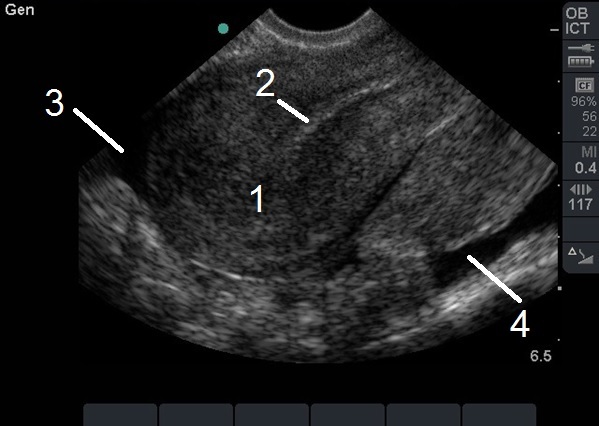

Bild: Transvaginaler (TV) Ultraschall des Beckens, ektopische Schwangerschaft, sagittal, leerer Uterus mit freier Flüssigkeit

1. Leerer Uterus

2. Endometriumstrfn.

3. Freie Flüssigkeit im rektovesikulären Raum, anterior

4. Freie Flüssigkeit im rektovesikulären Raum, posterior